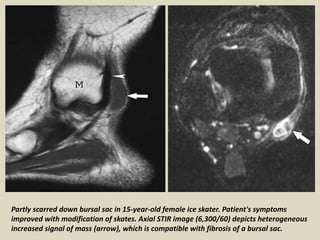

Partly scarred down bursal sac in 15-year-old female ice skater. Patient's symptoms

improved with modification of skates. Axial STIR image (6,300/60) depicts heterogeneous

increased signal of mass (arrow), which is compatible with fibrosis of a bursal sac.

Partly scarred downbursal sac in 15-year-old female ice skater. Patient's symptoms improved with modification of skates. Axial STIR image (6,300/60) depicts heterogeneous increased signal of mass (arrow), which is compatible with fibrosis of a bursal sac.